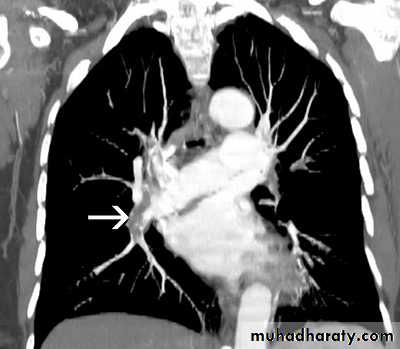

Massive pleural effusion with mediastinal shift to the left.

(A) Chest radiograph

(B) CT coronal reconstruction. A massive effusion displaces the mediastinum to the left. CT shows the important pleural effusion together with the enhanced atelectatic left lung.

Note also the depression of the right hemidiaphragm (arrows).